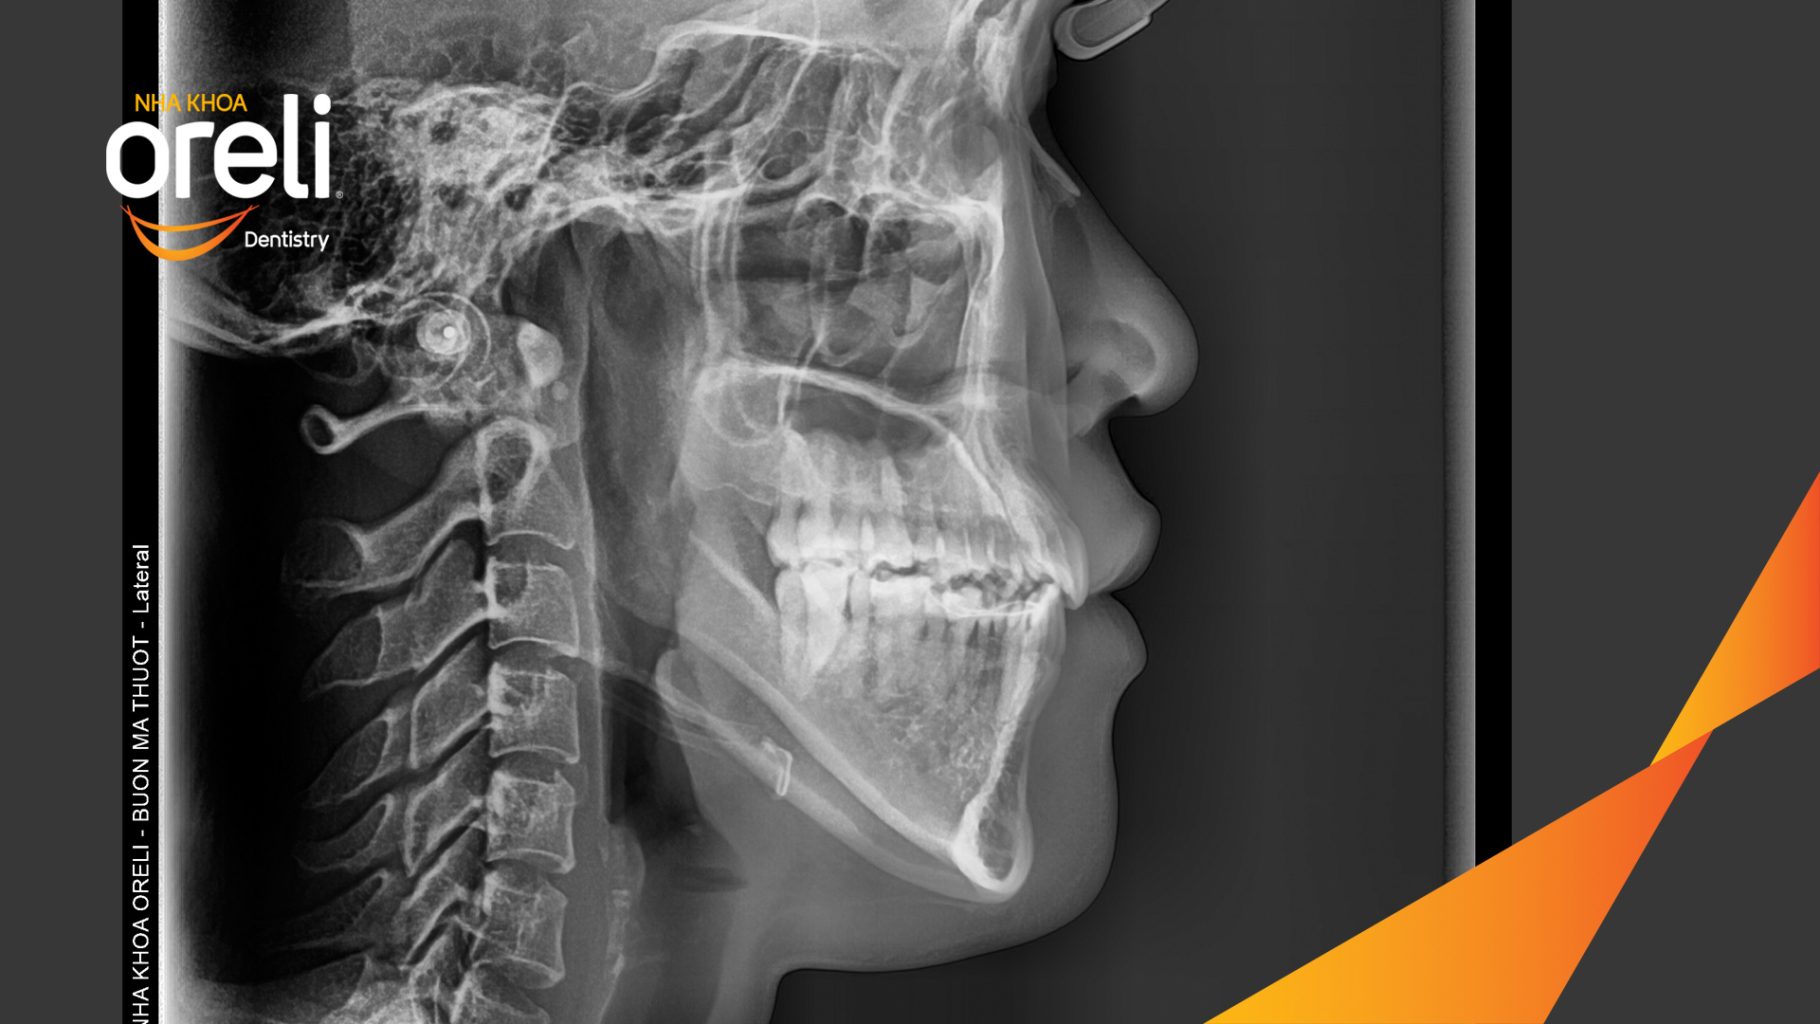

Hành trình thay đổi nụ cười ca lệch khớp cắn hạng 3, hàm dưới trượt ra trước và nhô xương hai hàm.

Hình ảnh thực tế